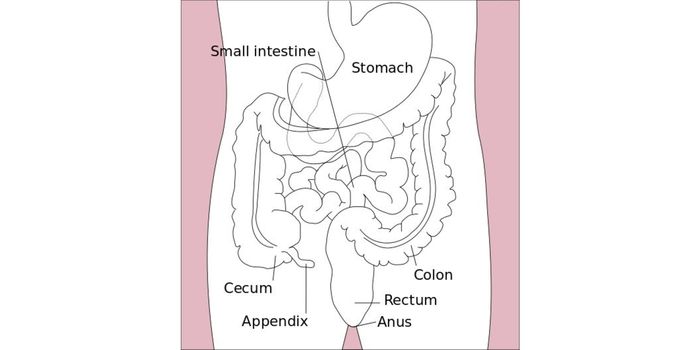

AUG 31, 2016VideosRunners often experience a condition known as "runner's diarrhea," which is when the person engaging in the activity exp ...

MAR 20, 2018VideosYou might've heard the old wives' tale about how swallowing chewing gum is bad because it'll stay at the bottom of your ...